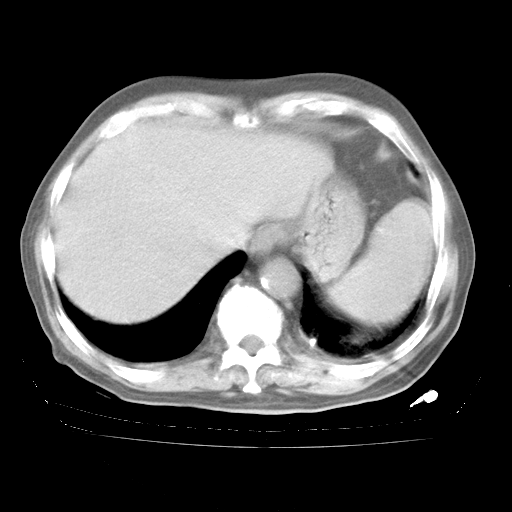

4月28日肺部CT

腹部B超:胆囊壁增厚,肝、胆、胰、脾、肾无异常,肠系膜淋巴结、腹膜后淋巴结无增大。